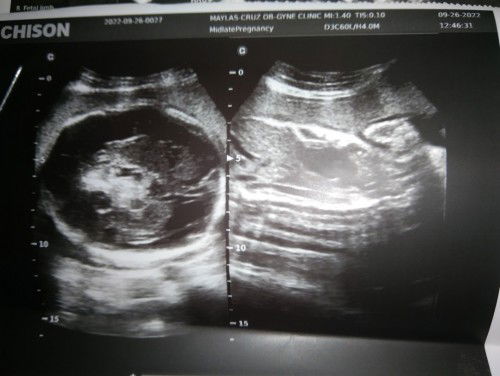

Hi mga mi . Share ko lang nag pa ultrasound ako kanina may napansin Yung ob ko mas Malaki daw ulo ni baby KESA sa katawan .. 28weeks nadaw dapat ako ngayon Kaso ang size ng ulo ni baby is pang 37weeks . Under observation daw mukhang may tubig sya sa ulo pero not sure padaw.. Need close monitoring Muna daw kami sa baby wala naman inadvice sakin Yung ob kung ano gagawin monitor lang talaga . Need ko opinion nyo momsh..